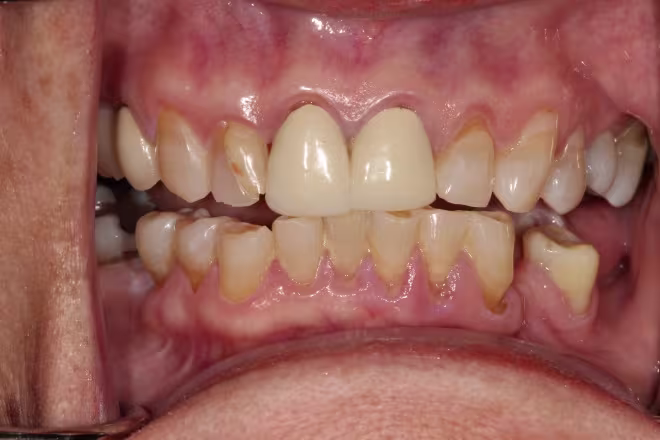

Intraoral: A well-defined firm hyperkeratotic mass is noted originating from the FOM overlying the L sublingual fold (~ 1 cm x 1.5 cm) adjacent to #20. The mass has a distinct indentation that corresponds well with the lingual aspect #20 (Figures 1 and 2). An excisional biopsy is performed and the tissue submitted for histopathologic examination.

Figure 1. Anterior view of occlusion.